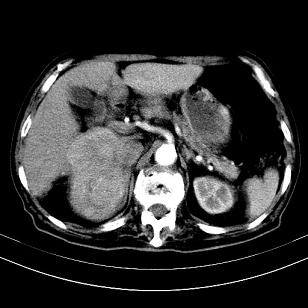

标题: CT19407:肝内还是肝外原发性肿瘤??

男,63岁,高血压病史40余年,

来源-右侧肾上腺。

考虑右侧肾上腺巨大占位;恶性?

肝内多发低密度找;转移瘤?

考虑右肝后叶肝癌(部分外生)伴肝内多发性转移;右侧肾上腺区恶性肿瘤并肝转移待排。

考虑右侧肾上腺肿瘤并肝内多发转移。右侧肾上腺呈“八”字形,包括内侧枝及外侧枝,内侧枝受压,考虑外侧枝原发肿瘤。”

考虑肝右后叶肝癌(部分外生)伴肝内多发性转移;不排除右侧肾上腺区恶性嗜铬细胞瘤并肝转移。